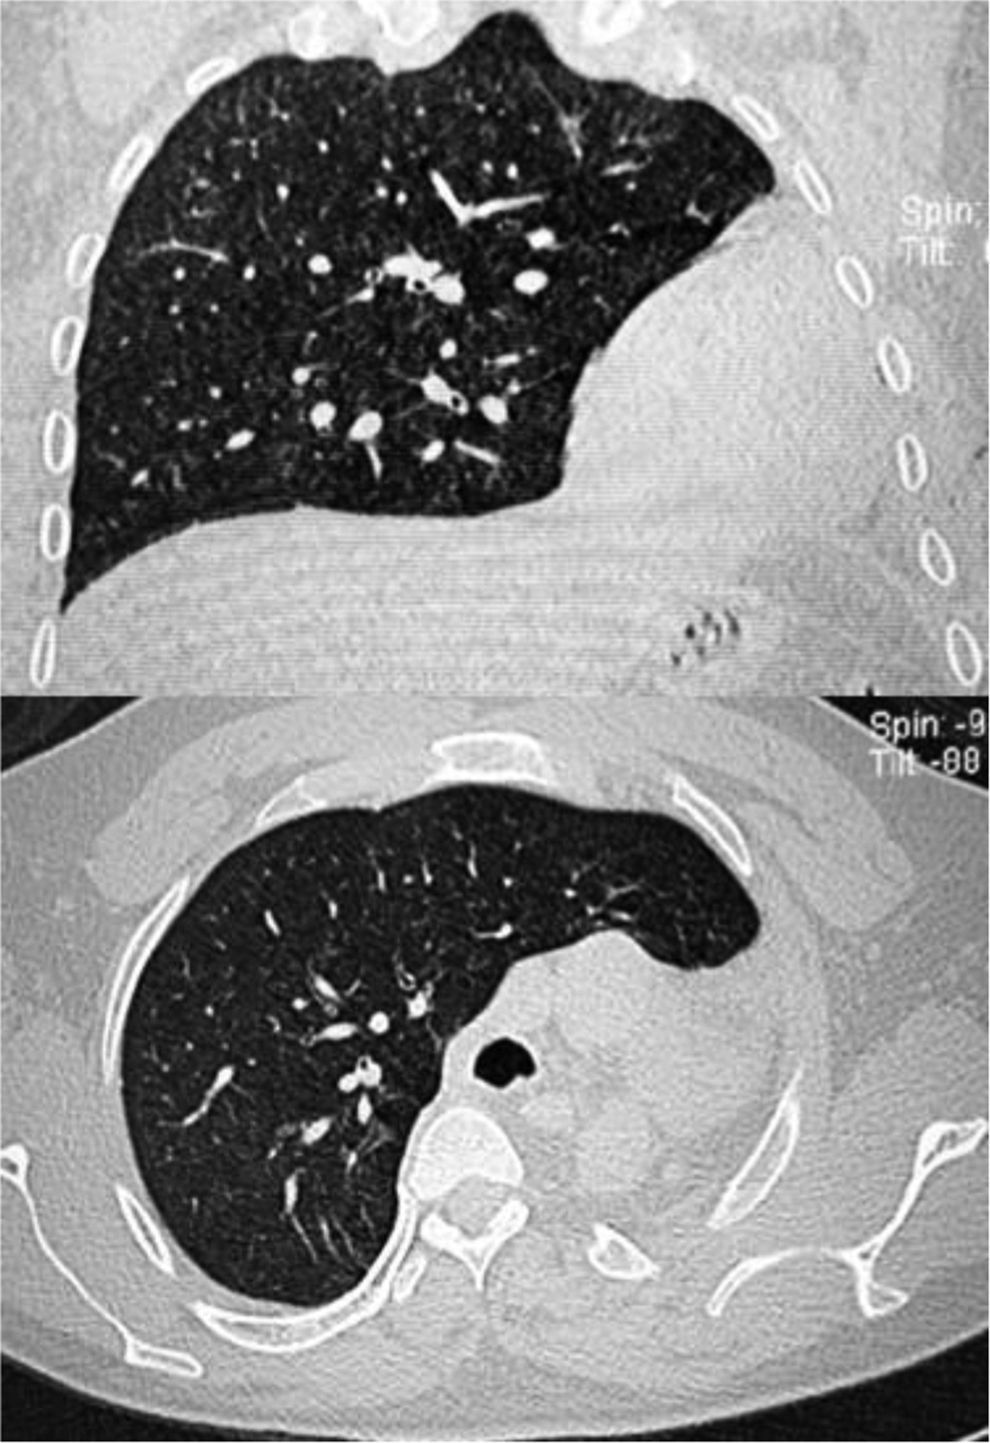

En la radiografía de tórax se observó la tráquea y el mediastino con notable desviación hacia la izquierda, con signo de columna vertebral desnuda y opacidad total del campo pulmonar izquierdo y hernia del pulmón derecho hacia la izquierda (fig. 1). Se realizó nueva toracocentesis diagnóstica sin obtener muestra, por lo que se solicita tomografía computada de tórax urgente por probable hemotórax coagulado, en la cual se observa ausencia de pulmón y arteria pulmonar izquierdos, coincidentes con la herniación de pulmón derecho sin alteraciones en el resto de parénquima. El corazón y los grandes vasos ocupan el hemitórax izquierdo (figs. 2 y 3), con asimetría de la caja torácica por disminución de los espacios intercostales, sin evidencia de fracturas costales. Riñón en herradura con malrotación (fig. 4). Se realizó broncoscopia, observándose disminución del calibre de la emergencia de bronquio principal izquierdo en fondo de saco con obstrucción total. Se instilaron 40ml de solución salina a presión, sin evidencia de permeabilidad, en el fondo de saco del nacimiento del bronquio principal izquierdo con epitelio de coloración amarillo nacarado. La evolución fue satisfactoria, sin evidencia de daño mediato por el trauma y egreso del servicio. No fue posible el seguimiento del caso.

En la radiografía de tórax se muestra una opacidad total del hemitórax afectado e hiperplasia compensatoria del pulmón contralateral con desplazamiento mediastinal hacia el lado afectado. La angiotomografía de tórax es importante para confirmar la ausencia de parénquima pulmonar, bronquios y vasos pulmonares del lado afectado; este estudio se considera como el estándar de oro para el diagnóstico1-4,8,25,26. Sin embargo, es factible hacer el diagnóstico con TAC sin medio de contraste, donde se puede detectar la ausencia de la arteria pulmonar correspondiente y la presencia de hernia pulmonar hacia el hemitórax afectado, donde coincide con una opacidad hemitorácia uniforme y desviación del mediastino tal como se ilustra por Cavada et al.5, Boulton y Force7, Deleanu et al.18 y Kishu et al.20. En este caso no fue factible hacer el estudio contrastado por la corta estancia del paciente y no fue posible su seguimiento. La toracocentesis no está formalmente indicada; en este caso se practicó, y la aspiración de líquido hemático pudo obedecer a la lesión vasos intercostales.

El diagnóstico en este paciente se confirmó con la tomografía de tórax, que muestra ausencia de arteria pulmonar izquierda y ausencia total de parénquima pulmonar izquierdo; en la broncoscopia se observó un pequeño fondo de saco a nivel del nacimiento del bronquio principal izquierdo.